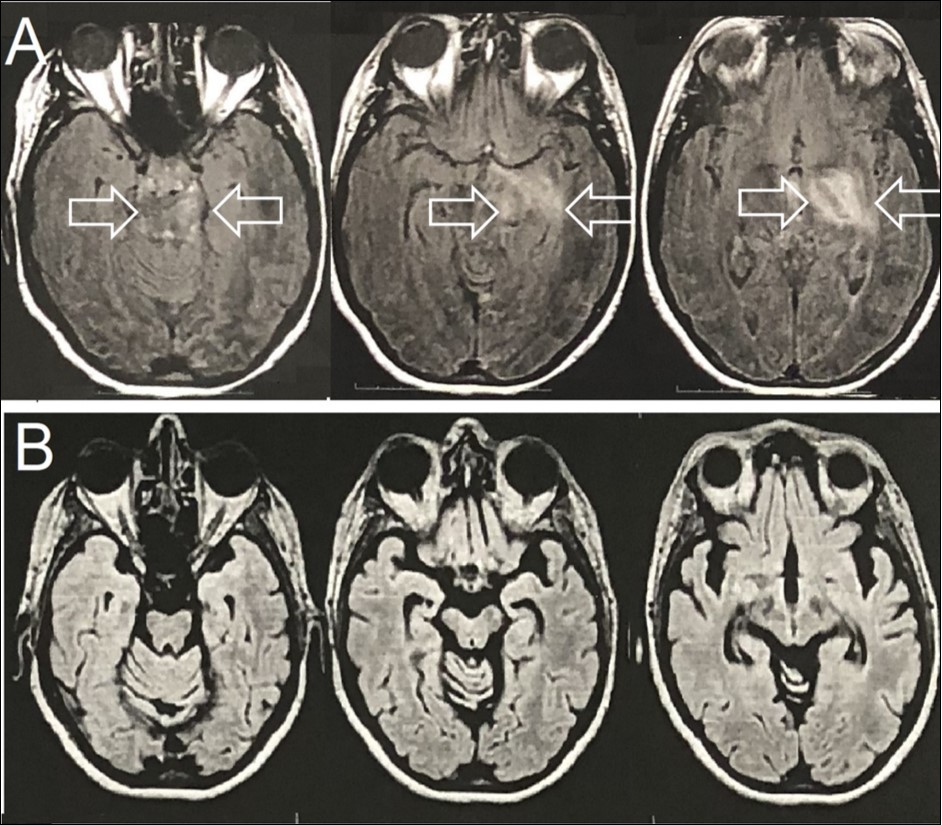

Family medical background was unremarkable. Brain T2-FLAIR magnetic resonance imaging (MRI) showed an expansive mass lesion at the left capsular nucleus region, with mesencephalic extension (Figure 1A). Cerebrospinal fluid analyses showed 15 cells, all of them lympho-monocytes, and protein of 45mg/dL (lumbar puncture). All other tests on spinal fluid were normal.

The patient was also referred to a neurosurgery department, where a brain biopsy was planned for diagnostic clarification. Meanwhile, the possible clinical diagnosis of BD was postulated and started treatment with 1 gram of methylprednisolone intravenously and for a period of 5 days with satisfactory results. Neurosurgery was then discarded. Therapeutic follow-up was instituted with azathioprine and after 2 months of treatment, due to abnormal liver function, anti-TNF-alpha (Infliximab) was was administered at 0, 2nd and 6th weeks and then every eight weeks; Despite cerebral atrophy, stable neurological evolution was found after 18 months of anti-TNF-alpha therapy (Figure 1B).

Figure 1.Brain Axial-FLAIR-MRI- (A) Expansive mass lesion with hyperintense signal in the left capsular nucleus region, with mesencephalic extension and enhancement by the paramagnetic agent (white arrows). (B) Complete improvement of the expansive mass lesion with the presence of brain atrophy.

Brain Axial-FLAIR-MRI- (A) Expansive mass lesion with hyperintense signal in the left capsular nucleus region, with mesencephalic extension and enhancement by the paramagnetic agent (white arrows). (B) Complete improvement of the expansive mass lesion with the presence of brain atrophy.